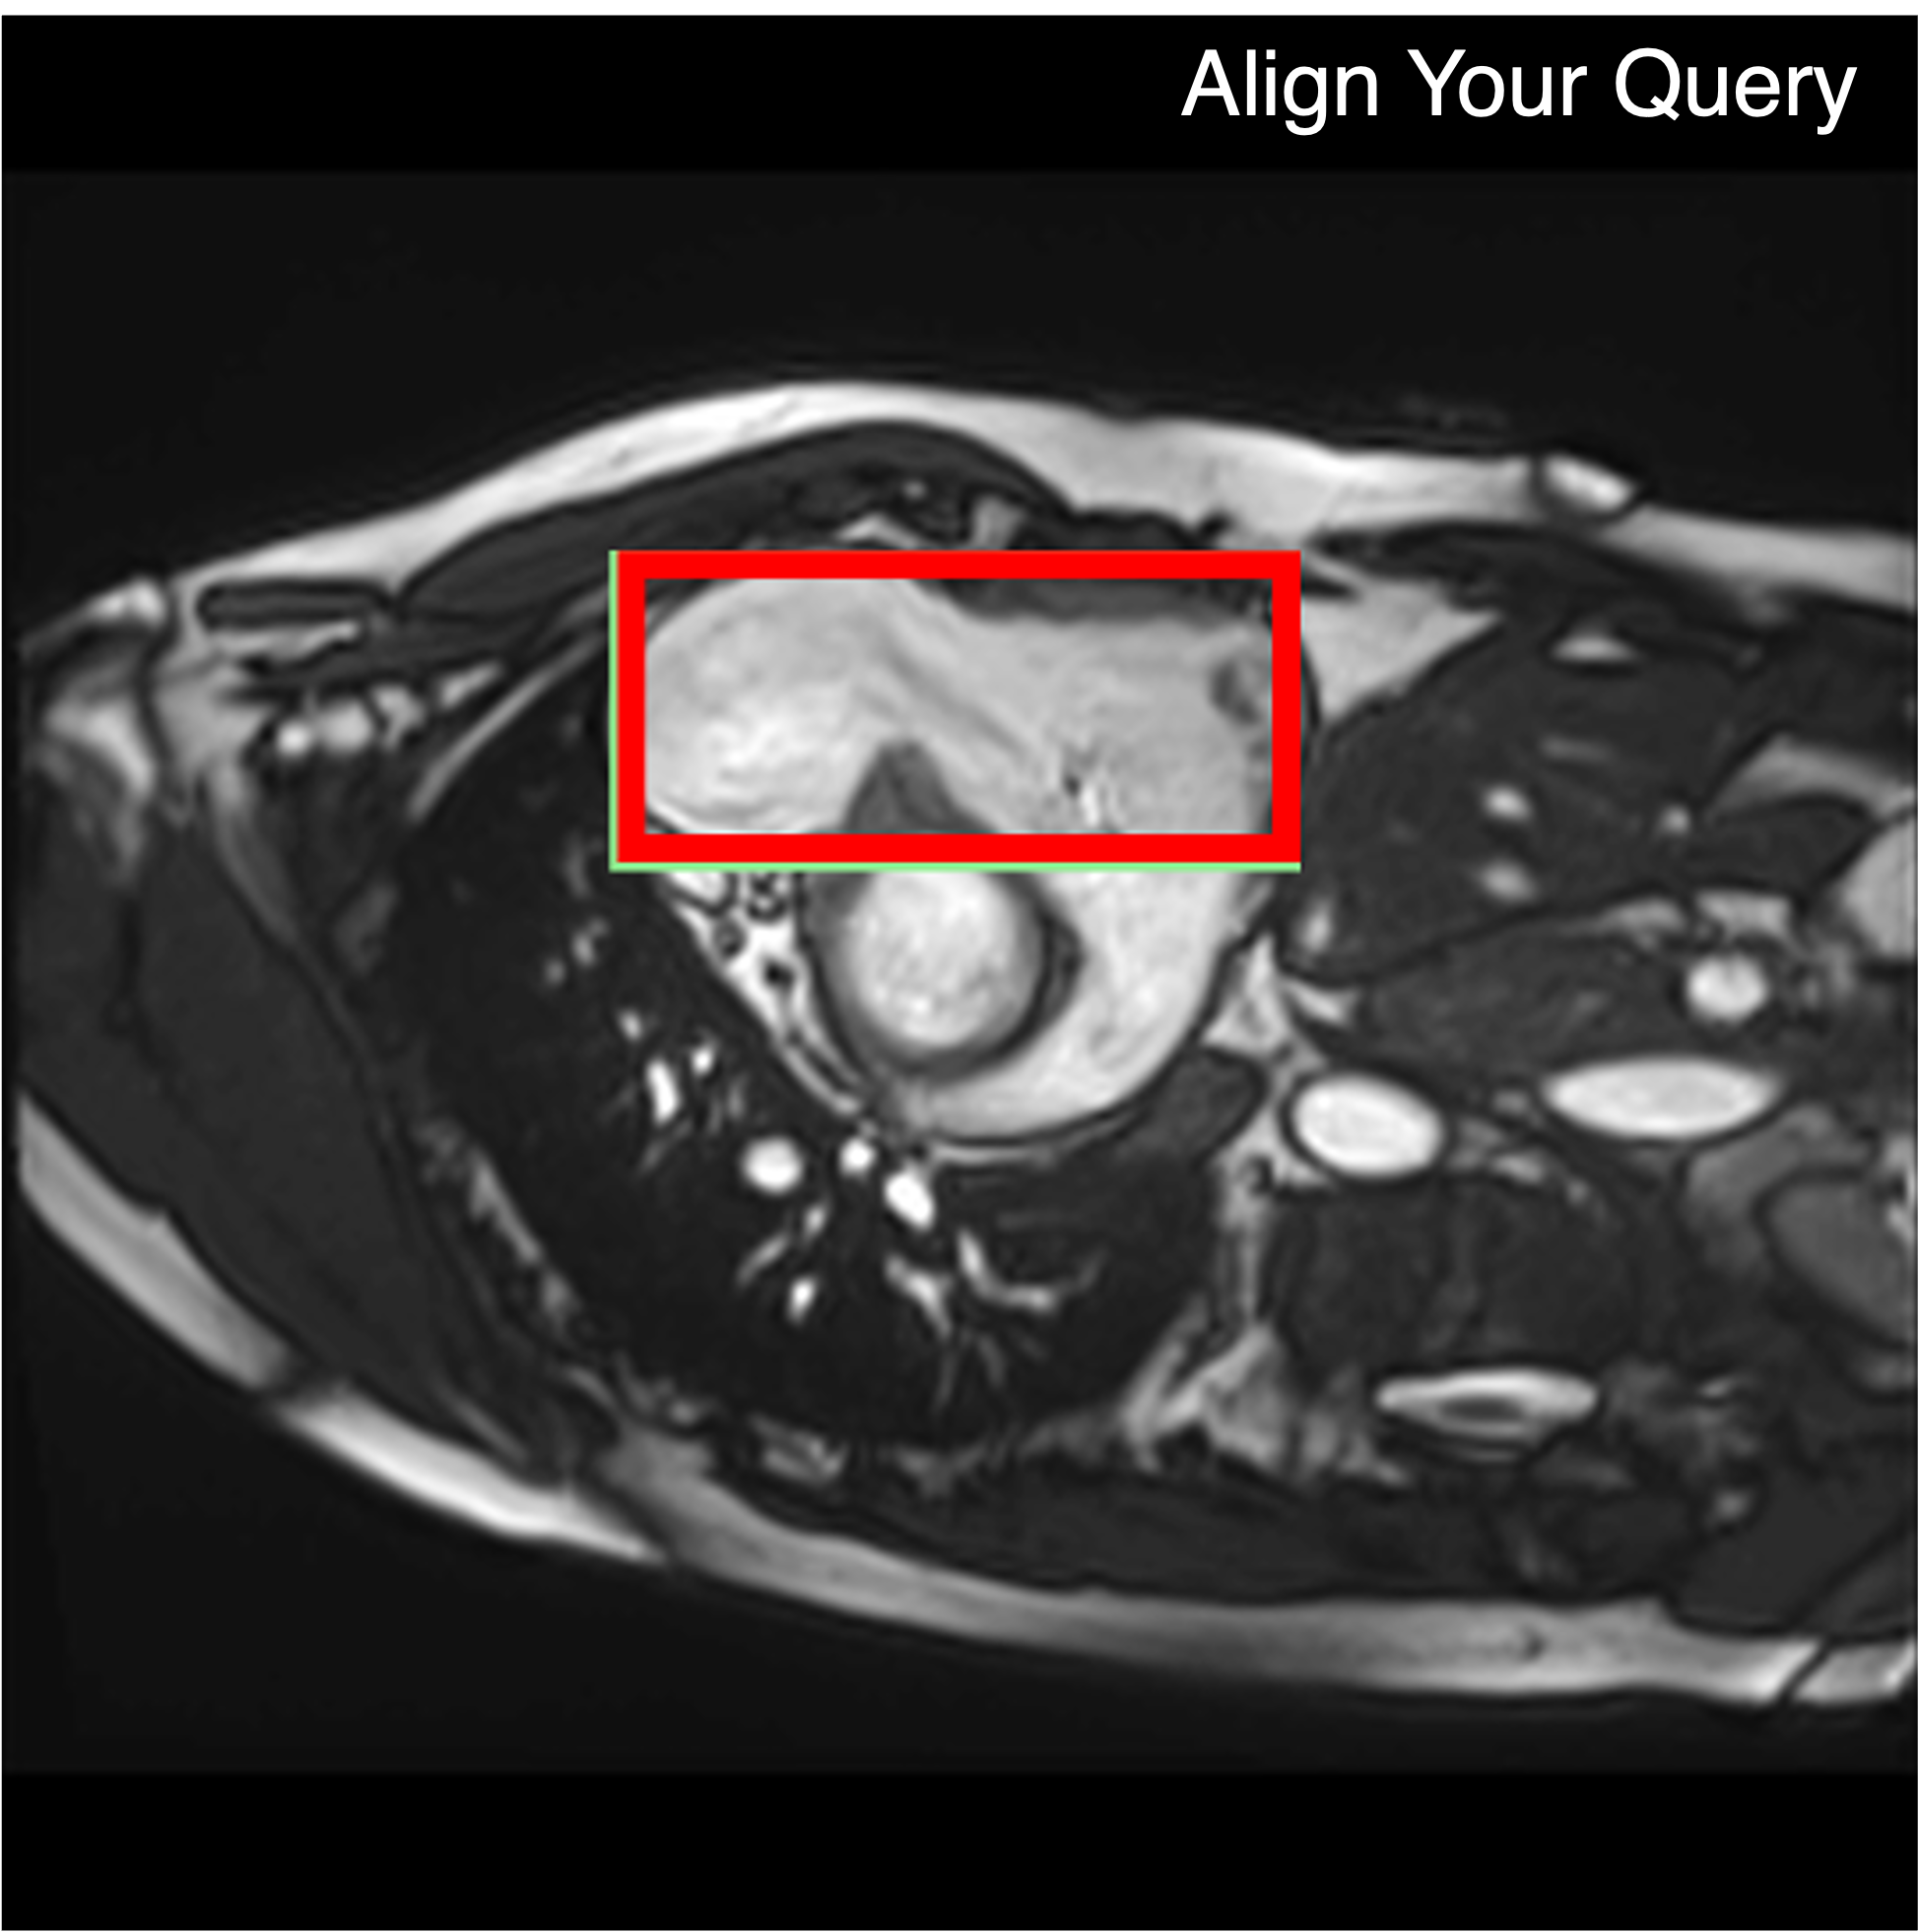

Qualitative comparison results

Qualitative Comparison. Comparison results between various state-of-the-art detection methods and the proposed method is shown above. Our method effectively leverages modality context to significantly enhance anomaly localization (red), compared to baseline results (blue). Ground truth bounding boxes are green. For cases where the bounding boxes are small, insets show an enlarged view of the highlighted yellow region.